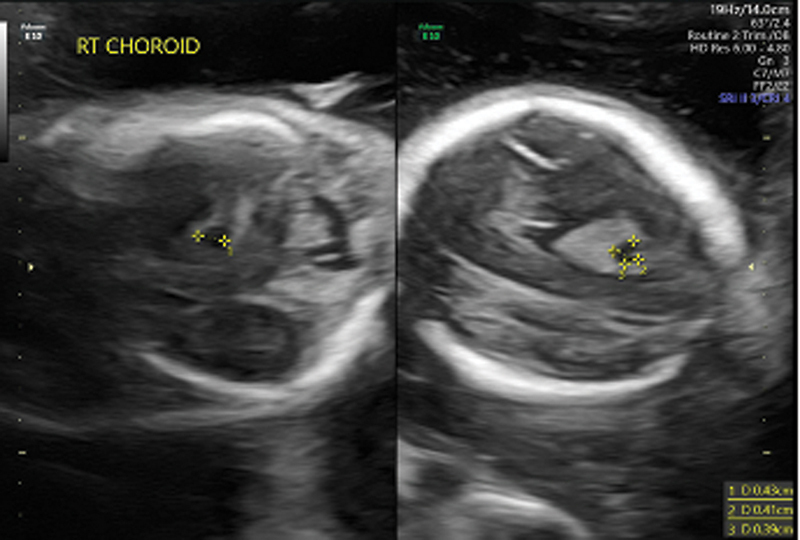

背景:很少有与努南综合征(NS)相关的Dandy-Walker畸形的报道。病例介绍:我们在此提出一个患有Dandy-Walker畸形(DWM)的晚期早产儿的病例,该婴儿接受了喂养困难的检查,并被发现患有NS。这是少数报道的DWM合并NS具有PTPN11基因突变的病例之一。结论:重叠的临床特征可能会掩盖婴儿多重病理的诊断。

Background: There are few reported cases of Dandy-Walker Malformation associated with Noonan syndrome (NS).

Case presentation: We herein present a case of a late preterm infant with Dandy-Walker malformation (DWM) that underwent a workup for feeding difficulty and was found to have NS. This is one of the few reported cases of DWM with NS having a PTPN11 gene mutation.